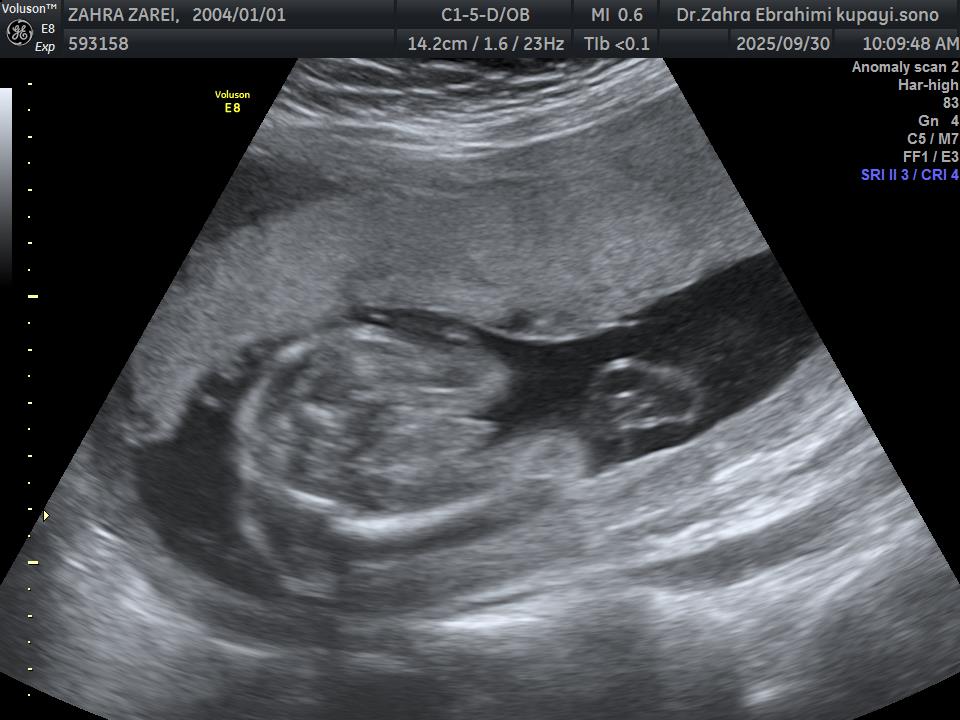

roz_13 مدیر استارتر عضویت: 1402/08/23 تعداد پست: 12 عنوان جنسیت 64 بازدید | 1 پست جنسیتش چیه به نظرتون؟ 1404/07/11 | 16:31 0 نفر لایک کرده اند ... گزارش تاپیک نامناسب